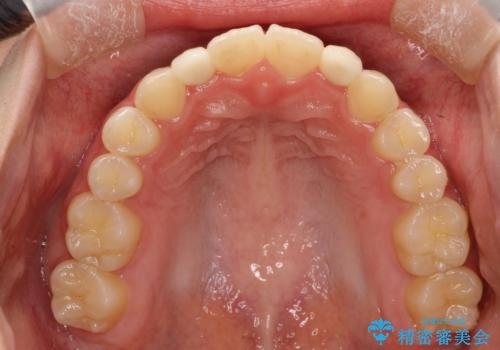

上あごの2番目の歯は矮小歯といって、生まれつき小さい歯となる事がよくあります。

このような場合、矯正によりスペースを集め、本来あるべき形態にセラミックで修正することもできます。

時間はかかりましたが、きれいな笑顔になりました。

かぶせ物の種類:PFZ standard